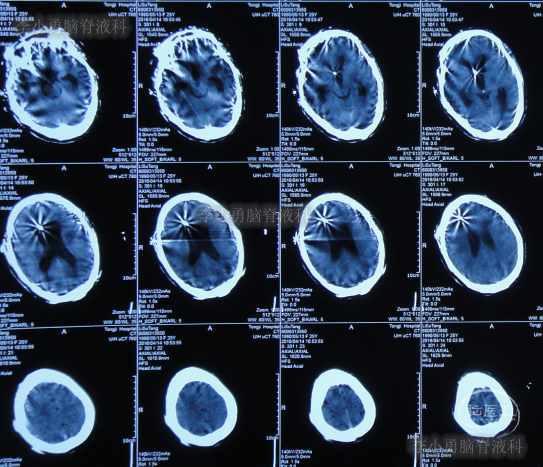

家属为进一步明确病因即2016年4月4日,第2次就诊并住入第二家的上海市静安区的某三甲医院,复查头颅影像后(图-3、图-4),给予按癫痫进行治疗。

图-3:2016年4月4日头颅CT